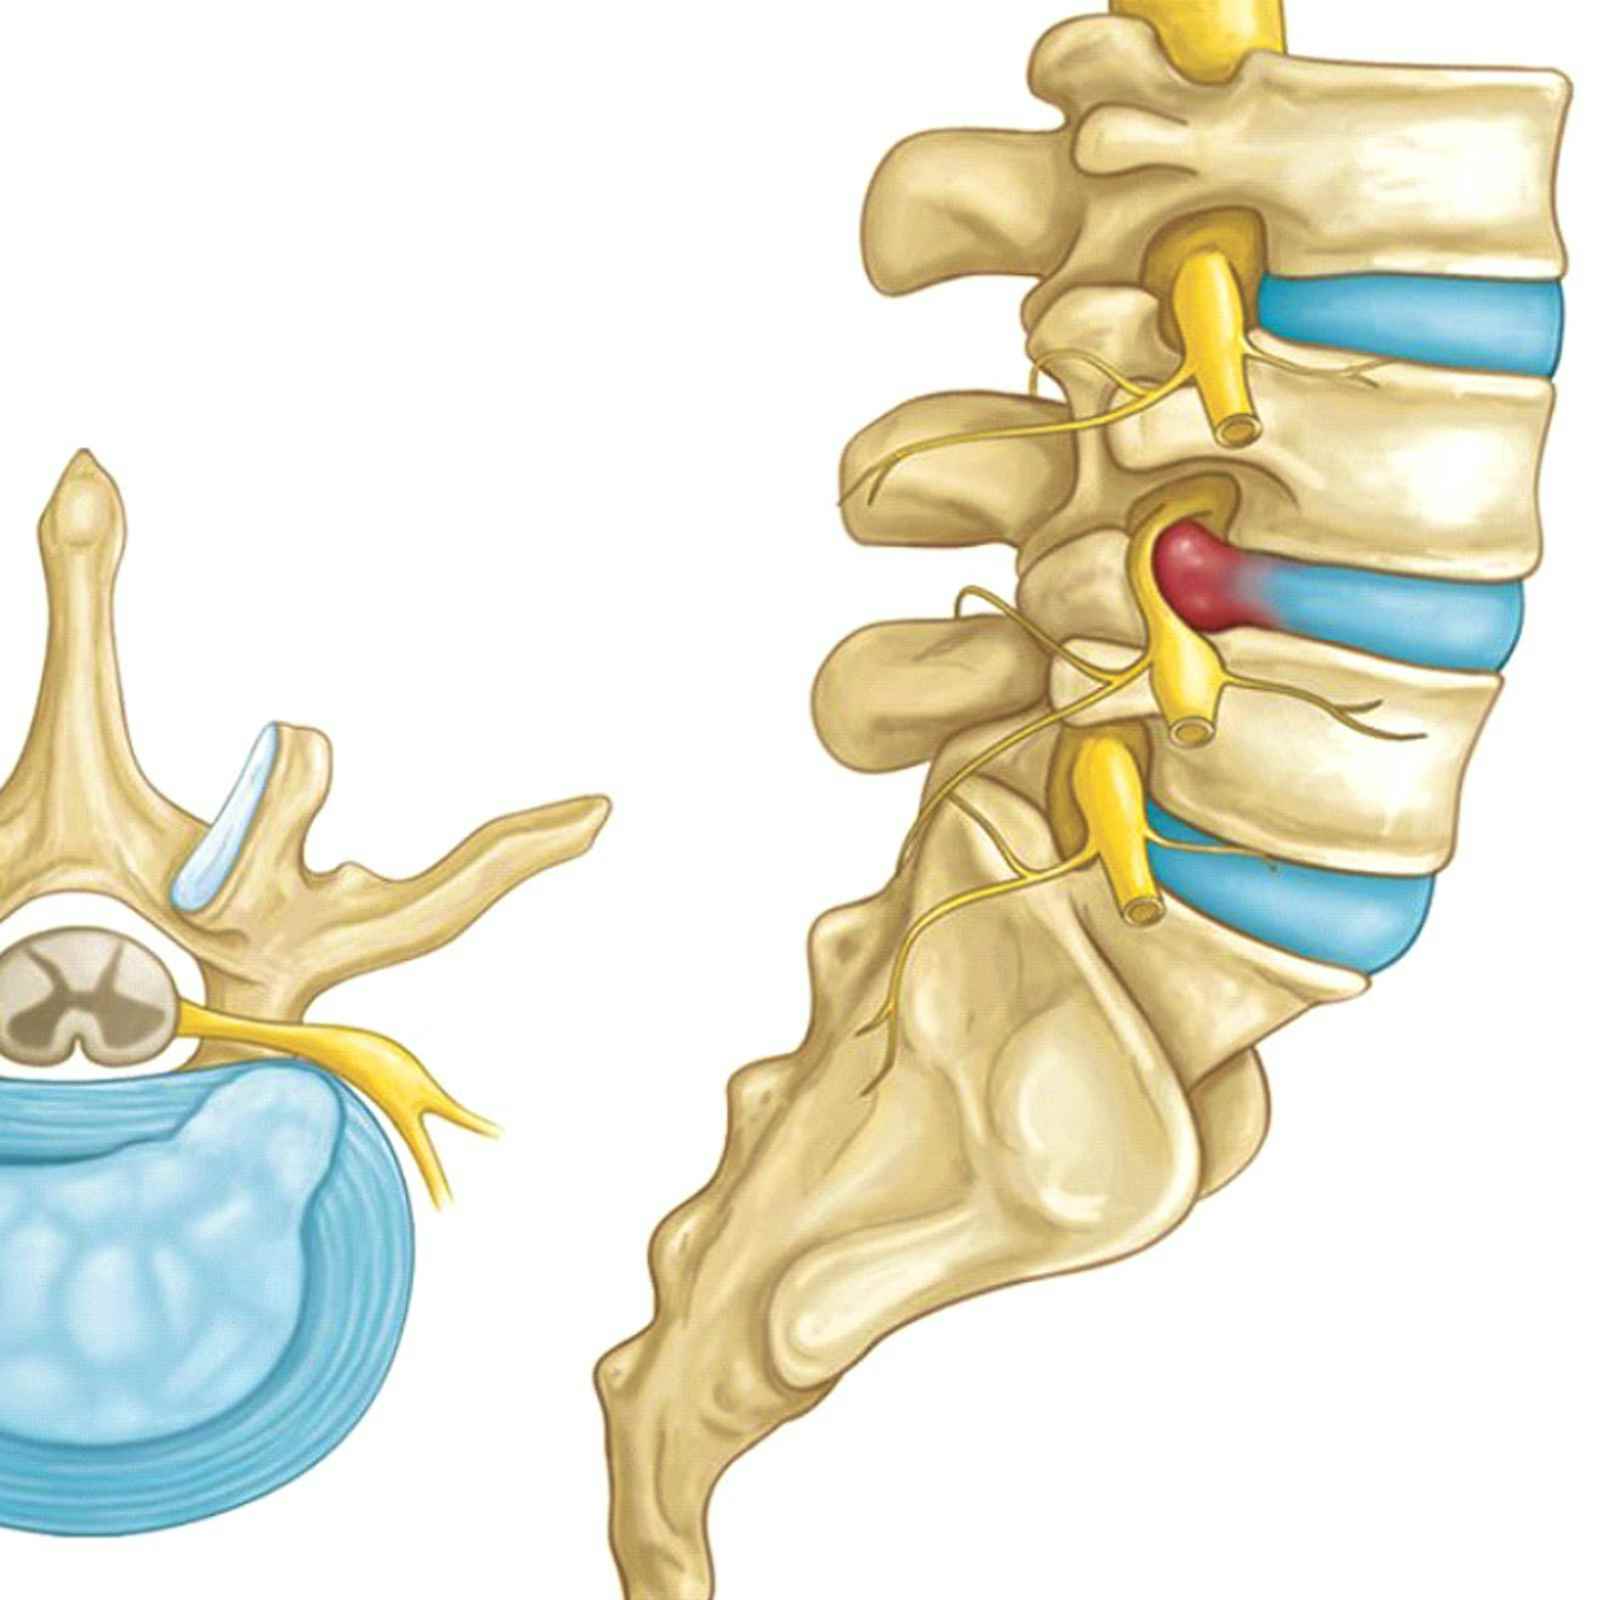

Позвонок Th10: анатомия и фото медицинских иллюстраций